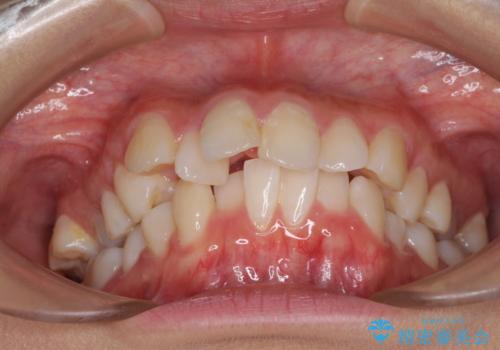

- 出っ歯とデコボコを気にして来院された患者様です。

口元の突出感を改善するため、上下左右第一小臼歯4本の抜歯を行い、ワイヤー装置による矯正治療を行うこととしました。

治療前の上下正中はずれていましたが、骨格的な上下左右差はあまり認められなかったため、正中を揃えて治療を終えることができました。